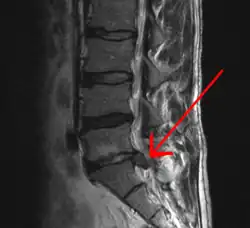

![]() МРТ-изображение межпозвонковой грыжи между сегментом L5 поясничного отдела и крестцом. | |

Грыжи относительно редко требуют хирургического вмешательства, тем не менее в США ежегодно проводится более 200 тысяч, а в Германии — 20 тысяч вмешательств. В 48 % случаев грыжи локализуются на уровне L5-S1 пояснично-крестцового отдела, в 46 % случаев — на уровне L4-L5, остальные 6 % — на других уровнях или на нескольких уровнях пояснично-крестцового отдела. Менее тяжёлое состояние — выпячивание ядра межпозвоночного диска без разрыва фиброзного кольца, называется протрузией.